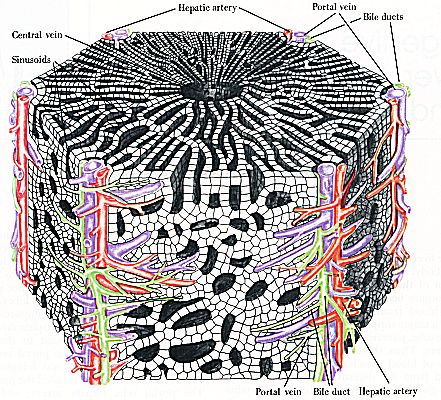

The histology of the liver is usually described on the basis of smaller units, called liver lobules. The most common description is that of the classic liver lobule, which consists of a number of liver cells (hepatocytes) surrounded by connective tissue. Such a liver lobule is usually hexagonal, with a central vein in the middle. The liver cells are arranged in plates with blood filled spaces, the sinusoids, in between the various plates of cells. At many of the corners of these hexagonal lobules, triads are found. Each consist of a bile duct, vein (branch of portal vein), and artery (branch of hepatic artery).

Fig RR472-01

Ross and Romrell p. 472